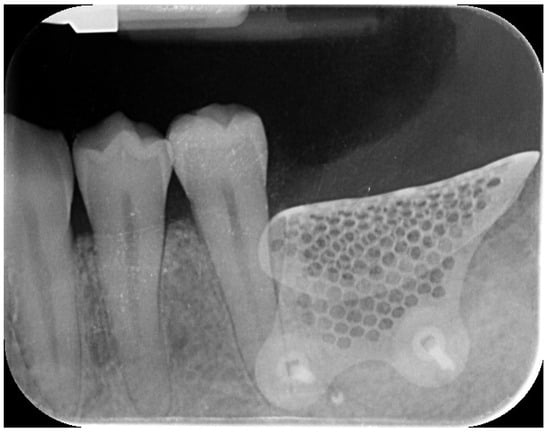

Nine months later, a periodical radiograph (Figure 6) and clinical examination confirmed adequate bone regeneration. Two implants (Osstem TSIII SOI, 4.5 mm in diameter and 10 mm in length; Osstem Implant Co., Ltd., Seoul, Republic of Korea) with hydrophilic surfaces were placed under local anesthesia, using a fully guided (Figure 7), metal-sleeve-free surgical template (OneGuide, Osstem Implant Co., Ltd., Seoul, Republic of Korea).

Figure 6. Postoperative intraoral radiograph.

Figure 7. Virtual implant planning. The implant positions were planned according to the prosthetic wax-up.

Notably, the buccal portion of the titanium mesh was completely covered by newly formed cortical bone, allowing for only a partial removal of the mesh prior to implant placement (Figure 8).